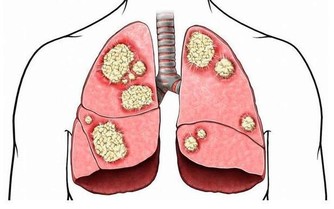

心臟病是全世界的頭號死亡原因,所以任何人都要了解它的風險性,

特別是如果你患有2型糖尿病,尤其如果你是女性。

因為,患有糖尿病的成年人死於心臟病的可能性,是沒有心臟病的成年人的兩到四倍。

雖然心臟病和糖尿病似乎不相關,但實際上有幾個重疊的原因和症狀。

大多數患有心臟病的人都有高血壓、高膽固醇、吸煙、飲食不佳、缺乏體力活動或心臟病家族史等因素。

而患有糖尿病的人,通常也有高血壓或高膽固醇,這使他們出現心髒病的風險更高。

而且,糖尿病是“擊潰血管的最後一根稻草”,當一個人在高血壓或膽固醇升高的情況下出現高血糖時,就像在原本已經脆弱不堪的血管上火上加油,這導致血管更加狹窄。